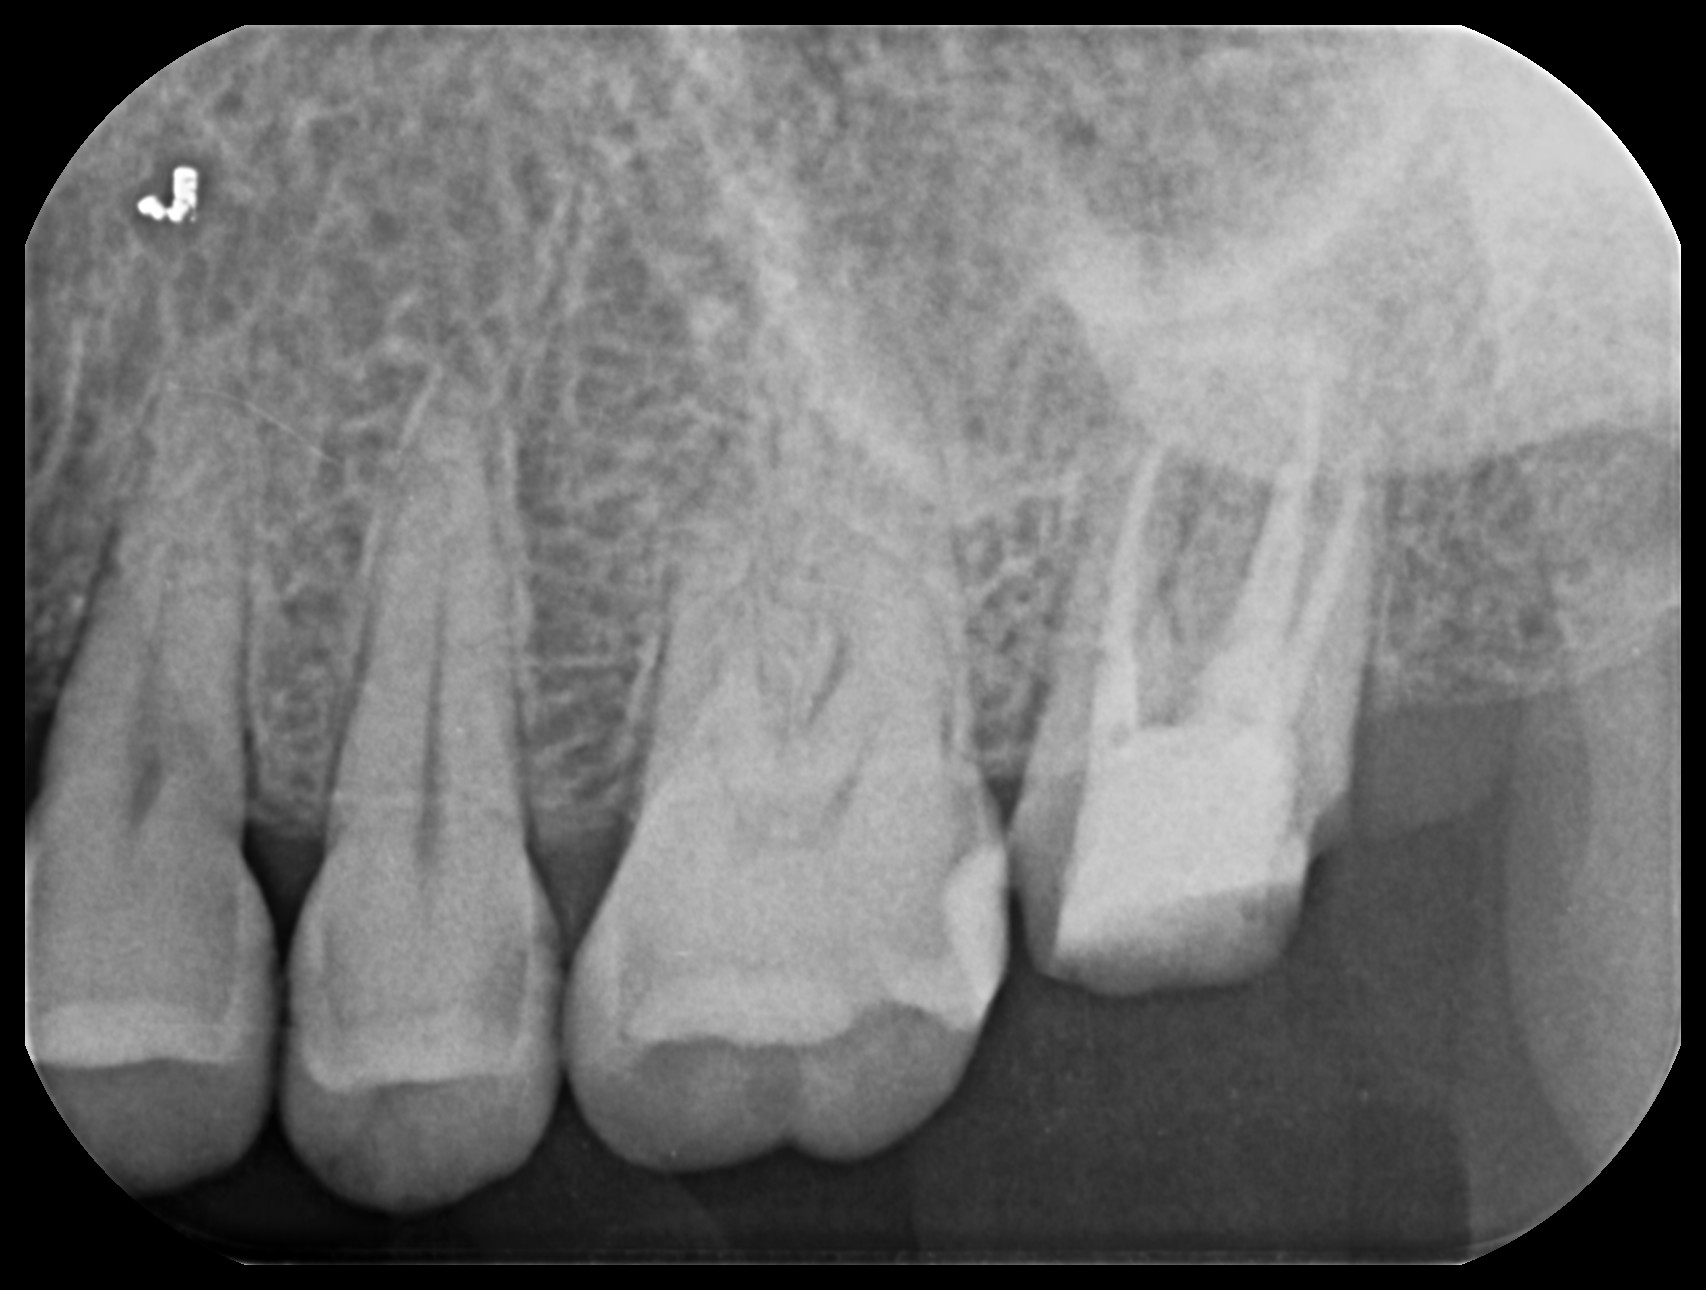

治療前後のレントゲン比較

左が初診時、右が治療後4ヶ月経過した時点でのレントゲンです。

根尖部の黒く抜けていた部分がなくなっているのが確認できます。